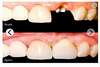

Prothèse fixe : Couronne

Prothèse fixe : Bridge